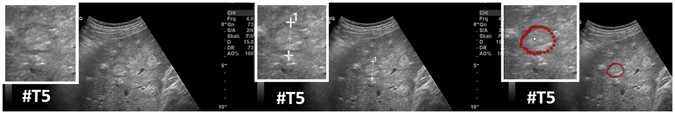

Figure 7

Segmentation results (manual/interactive) of a hyperechoic appearing metastasis with a hypoechoic halo (metastasis of a colon cancer), where the metastasis shows a very low contrast to the surrounding liver parenchyma. The native image with a zoomed view of the metastasis is presented in the left image. A manual measurement of the maximal metastasis diameter (white dotted line between two white crosses) is shown in the middle image. Finally, the rightmost image presents the interactive segmentation results (red dots) with the corresponding user-defined seed point (white). Note: figure adapted from26.